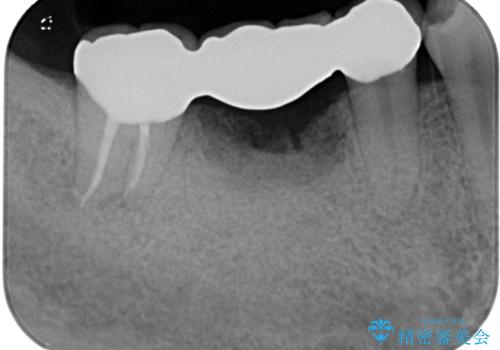

抜歯後も膿の出口が消えず、一番奥の歯を診察したところ神経組織の反応がなかったため、根管治療を行うこととしました。

再度の歯を根管治療したため、抜歯した部位の補綴治療は、強度の問題からブリッジよりもインプラントをおすすめしましたが、患者様希望によりブリッジを選択しました。

一番奥の歯は歯肉から露出している高さが少なく、クラウンを装着する不十分であったため、歯冠長延長術を行うこととしました。